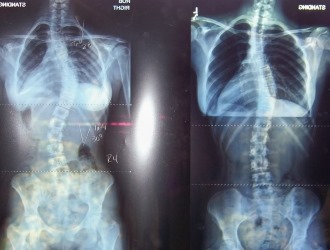

При сколиозе наблюдается асимметричное дыхание – основная часть воздуха попадает в выпуклую сторону грудной клетки, что приводит к усилению искривления позвоночника и образованию реберного горба.

Дыхание человека, страдающего от сколиоза, изначально нарушено из-за деформации грудной клетки: вдох с выпуклой стороны оказывается более глубоким, чем с вогнутой. Врач должен провести изометрическую оценку дефекта и разработать комплекс корректирующих упражнений.